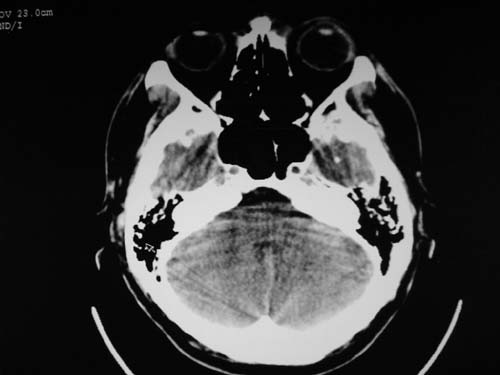

脑中线内血肿,是硬膜下的吗?

脑中线内血肿——硬膜下血肿。

脑中线内血肿——硬膜下血肿。我们一般认为中线即可是硬膜下,也可是蛛网膜下腔的。边缘锐利,张力高的考虑硬膜下的,边缘模糊的,考虑下腔的。如果有老师有肯定的答案,麻烦下给我发个短信

硬膜下血肿,有颅骨骨折

支持镰旁硬膜下血肿,颅骨骨折,头皮损伤.

这个病人年龄不小吧,右侧脑沟不清,中线结构稍有左移,右侧额颞顶及右镰旁硬膜下血肿,另有蛛血,骨折。

外伤后引起的颅骨骨折、硬膜下血肿、皮下血肿,颅骨骨折引起的矢状窦破裂,形成大脑纵裂内血肿。